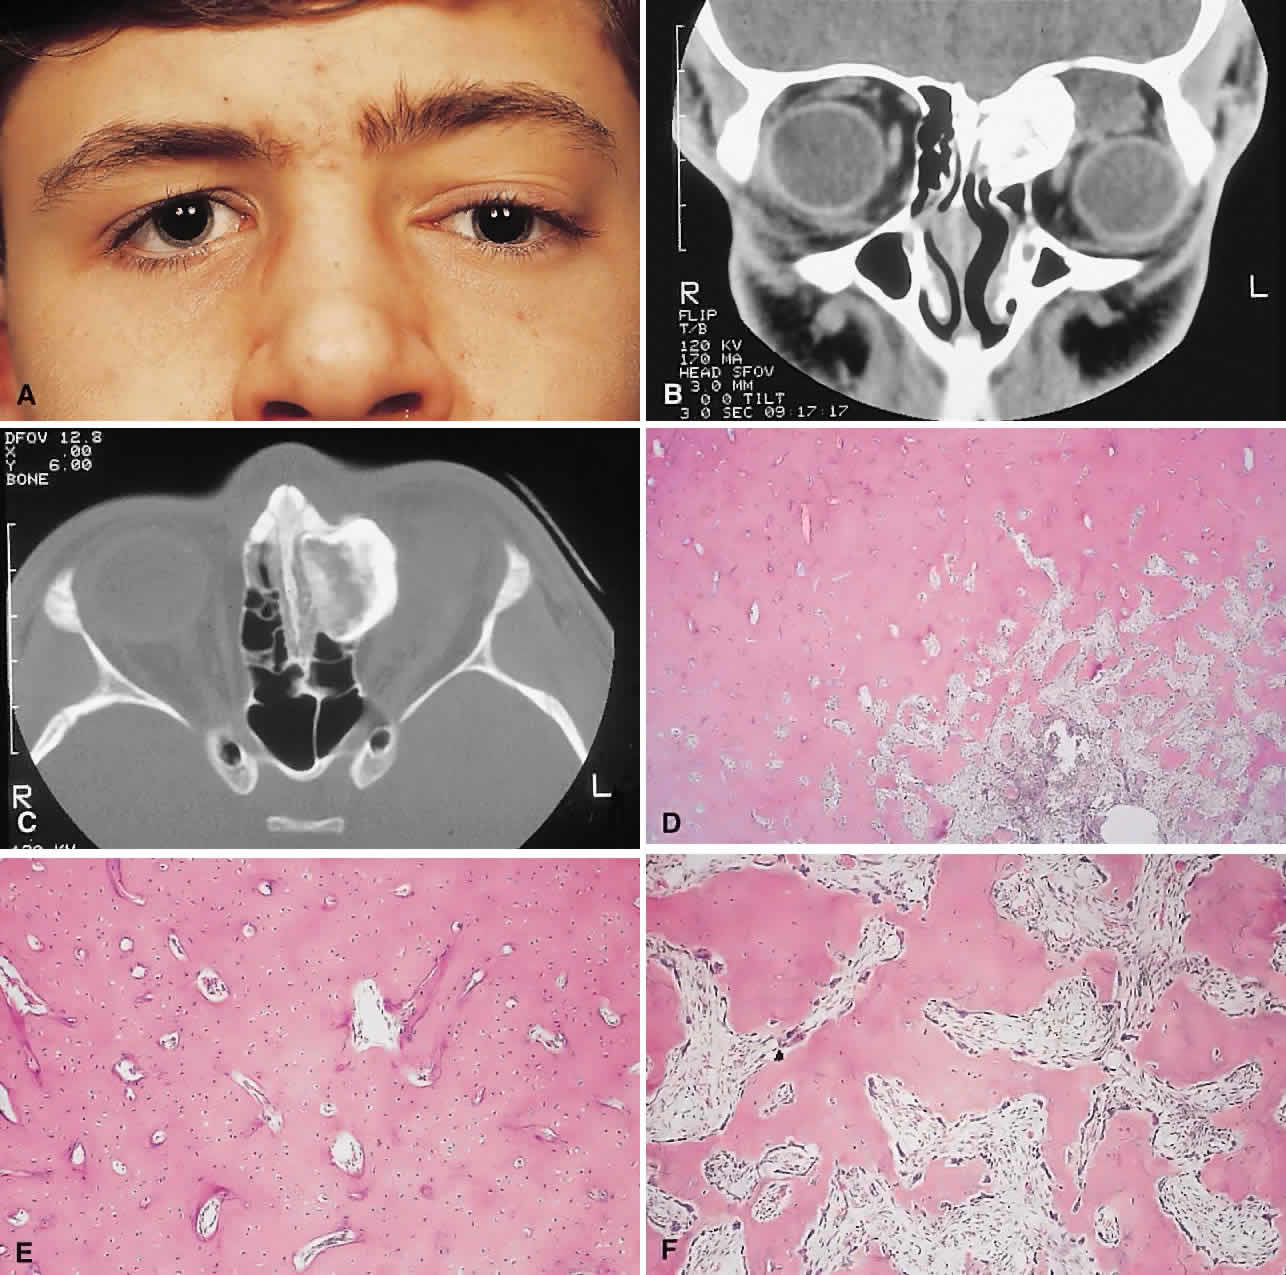

| The above clinical patterns correlate reasonably well with the following

clinicopathologic classification (see Table 1). BENIGN FIBRO-OSSEOUS AND CARTILAGINOUS LESIONS Osteoma A true osteoma is a tumor-like mass of bony tissue that is histologically similar to normal bone. Its pathogenesis remains unclear, although traumatic, infective, or hamartomatous theories have been proposed.4 Others have suggested that osteomas arise exclusively at the junction of bones of cartilaginous and membranous origin.5 None of these theories account for the facts. The most common sites of origin are the paranasal sinuses, skull, and facial bone. The fact that osteomas were found in 0.42% (15 of 3510) of plain sinus radiographs reflects their prevalence.6 In the sinuses, 50% occur in the frontal sinus, with the ethmoid, maxillary, and sphenoid involved in descending order of frequency. Most orbital osteomas are secondary invaders from adjacent sinuses, but on occasion they arise primarily in the orbit. In contrast to the sinus distribution, however, orbital osteomas appear to have a roughly equal origin from the ethmoid, frontoethmoid, or frontal regions.7,8 This may reflect the relatively thin barrier to expansion posed by the medial orbital wall. The age range runs the gamut from 10 to 82 years, with the highest prevalence in the fourth and fifth decades. Males and females are represented equally.7–9 PRESENTATION. Most sinus osteomas are solitary and asymptomatic.6 However, when large enough to encroach on the orbits, a gradual evolution of proptosis or globe displacement over many years can occur (Fig. 1). There may be an associated headache as a result of expansion of the overlying cortex and periosteum, and a bony mass is often palpable in the superior or superomedial orbit. Obstruction of the sinus ostia may lead to chronic sinusitis or mucocele. Less common features include an acquired Brown syndrome,10 gaze-evoked amaurosis or pain,4,11 subluxation of the eye12 and erosion leading to orbital emphysema, or cerebrospinal fluid rhinorrhea.13 The sphenoid sinus, although a rare site, is significant because even a small lesion may lead to an orbital apex syndrome. An uncommon but important systemic association is Gardner's syndrome. This autosomal dominant syndrome of osteomas, soft tissue tumors, and peripheral congenital retinal pigment epithelial hypertrophy also includes the development of colonic polyposis with subsequent malignant transformation.14–16 Multiple osteomas are common; our one patient had only a single tumor, but one was also noted in the skull. Further, because bony lesions may predate the colonic pathology, patients with osteoma warrant a dilated funduscopy and referral to a gastroenterologist.17 IMAGING. The plain radiograph and CT appearances consist of an osteoblastic round or ovoid sharply circumscribed mass, usually arising in the sinus and invading the orbit. Tumors growing in a sinus conform to its internal contour and often have a bosselated surface. Osteomas may be sessile or pedunculated and generally have a diameter of 1 to 5 cm.18 Bone window settings on CT imaging often show a very dense periphery with a more cancellous internal structure. However, the relative proportions of the two densities may vary with the size of the lesion. HISTOPATHOLOGY. It is important to distinguish osteomas from reactive osteomatous responses to infection, trauma, and chronic inflammation. The clinical and radiologic appearances are often invaluable in this regard. Macroscopically, true osteomas have smooth or bosselated contours with a glistening white or pinkish coloration. A covering of mucoperiosteum or periorbita may be seen, depending on the site of origin.18 Osteomas have been classified histologically into three groups depending on the predominant tissue present: compact (cortical, ivory), cancellous (trabecular, spongy), and fibrous. Fu and Perzin19 have postulated that the histologic type is partly dependent on the age of the lesion, with the compact group representing the most mature and the fibrous the least. The fibrous subtype may, in fact, be part of a continuum incorporating ossifying fibroma and fibrous dysplasia. The compact areas resemble normal cortical bone with dense bony areas and haversian systems. However, there are subtle differences in the arrangement of the haversian canals, which is often evident to the experienced bone pathologist. The cancellous areas consist of anastomosing trabeculae with an intervening fibrovascular stroma. Fatty and hematopoietic elements may also be present in the stroma, as well as evidence of osteoblastic activity along the trabeculae. The fibrous region is made up primarily of loose fibrovascular tissue with a few irregular bony trabeculae and osteoid elements. In our series of nine surgically treated cases, we noted that although the three types of tissue were present in varying admixtures, in all cases there was a remarkably consistent pattern of arrangement. The most peripheral zone was made up of compact bone; moving toward the center or base of the lesion, there was an intermediate zone of increased osteoblastic activity, osteoid, and vascularity. The innermost region consisted of a loose fibrous stroma with a greater number of blood vessels, few trabeculae, and many plump osteoblasts. This configuration has been described previously by Albert and associates20 and illustrates the growth of these lesions. The outermost zone presumably represents more mature bone, and the activity seen centrally suggests that this is where growth is initiated. This implies that extirpation of the central region is probably required to prevent recurrence. It may also explain why leaving residual peripheral areas does not usually lead to regrowth. Finally, the histologic subtyping into compact, cancellous, and fibrous lesions probably has little practical significance, because there appears to be no correlation with the clinical course. MANAGEMENT. Generally, asymptomatic osteomas can be treated conservatively. The only possible exception to this is in the sphenoid sinus: it is technically easier to remove a small lesion in this location before it has encroached on the orbital apex and optic canal. If symptomatic and located in the anterior orbit, osteomas can be removed through an anterior orbitotomy. For anterior ethmoid tumors in the superomedial orbit, a modified Lynch incision is often used. Excision can sometimes be aided by coring the lesion and collapsing the cortex for removal. For more posterior tumors, involving the roof or cribriform plate, a combined orbitocranial approach using a bicoronal incision is favored.21 Recurrence is rare, even after a partial resection. Fibrous Dysplasia Fibrous dysplasia is a benign disorder in which proliferation of fibrous tissue and osteoid replaces and distorts medullary bone. The cause is unknown; past theories have included a maturation arrest at the woven bone stage, or hamartomatous proliferation.22 More recently, the discovery of a postzygotic mutation in the G protein in McCune-Albright syndrome suggests that the bone dysplasia in these patients is a manifestation of a somatic mosaic state.23,24 There are three forms of fibrous dysplasia: monostotic fibrous dysplasia (MFD), polyostotic fibrous dysplasia (PFD), and McCune-Albright syndrome.22,25 MFD accounts for 75% to 80% of cases, of which 20% affect the craniofacial bones. In the skull, the frontal bone is most commonly involved, followed by the sphenoid and ethmoid. Most patients with orbital involvement have MFD, although the disease has generally spread to contiguous bones by the time the patient comes to medical attention. PFD makes up 20% of all cases; half of these patients have head and neck involvement. McCune-Albright syndrome occurs largely in females and incorporates the triad of PFD, sexual precocity, and cutaneous pigmentation.26 This pigmentation appears as brown macules, usually six or fewer, with irregular “coast of Maine” borders.27 Fibrous dysplasia is generally recognized before age 30, although mild or asymptomatic cases may escape detection into late adult life.28 The gender distribution is roughly equal in MFD; there is a female predilection in PFD. PRESENTATION. The site and the extent of disease are the major determinants of symptomatology. Facial asymmetry, proptosis, and globe displacement evolving over many years are the most common manifestations (Fig. 2). Nasolacrimal duct blockage, diplopia, nasal obstruction, malocclusion, raised intracranial pressure, and cranial nerve palsies also occur.25,28–30 Acute or subacute compressive optic neuropathy can arise as a result of intralesional hemorrhage, sphenoidal mucocele, or secondary aneurysmal bone cyst.31 A more chronic visual loss, although less commonly reported, may occur as a result of compression in the optic canal or at the chiasm. On occasion, a superimposed ischemic neuropathy in the context of chronic compression leads to an acute on chronic deterioration in vision.32 This clinical spectrum is reflected in our experience of 10 cases. Changes in facial contour (7 patients), proptosis (7), globe dystopia (6), and decreased vision (3) were the major signs. Interestingly, seven patients also had pain, either localized to the orbit or described as a diffuse ipsilateral headache. Overall, the natural history is one of slow growth. Although this was previously thought to cease in adult life, there is evidence that fibrous dysplasia may progress well past the fourth decade.25 Rarely, malignant transformation to osteosarcoma, fibrosarcoma, chondrosarcoma, and giant cell sarcoma can occur; this is often signaled by a more rapid progression and increased pain. The incidence of this complication is estimated at 0.4% to 0.5%, rising to approximately 15% with prior radiation therapy.33 IMAGING. In the craniofacial bones, fibrous dysplasia tends to expand the bone, with thinning of the overlying cortex. The margins are poorly defined, and the dysplasia transgresses suture lines; the proportion of mineralized to fibrous tissue determines the degree of radiolucency. Most cases demonstrate a relatively equal mixture, resulting in a pagetoid appearance. Where the fibrous element is predominant, there may be cystlike areas; a preponderance of mineralized tissue, however, results in a homogeneous, sclerotic, “ground-glass” picture. Fries34 reviewed 39 patients with fibrous dysplasia of the craniofacial bones and found a pagetoid pattern to be most common (56%), followed by sclerotic (23%) and cystlike (21%) appearances. The primary differential is hyperostotic meningioma. This is distinguished by its occurrence in an older age group and by the presence of an associated enhancing soft tissue component, best seen on MRI. Also, meningioma often causes a more homogeneous thickening of bone, which in contrast to fibrous dysplasia does not leave a discernible cortical rim. MRI shows meningioma to have a signal isointense to gray matter on both T1- and T2-weighted images. Fibrous dysplasia, in contrast, tends to have a lower intensity on T1- and a heterogeneous signal on T2-weighted images.28,35 MRI may also have a role in fibrous dysplasia in the evaluation of mucoceles and recent hemorrhage. On occasion, Paget's disease and less commonly cystic bone lesions, such as localized Langerhans cell histiocytosis (eosinophilic granuloma), also enter into the differential diagnosis. Paget's disease arises beyond the age of 40, is usually bilateral, and radiologically may show areas of cotton wooltype density that are not usually seen in fibrous dysplasia. HISTOPATHOLOGY. Macroscopically, fibrous dysplasia consists of gritty, white-to-pink tissue, often with blood or serous-filled cystic areas. Histologically, there is a fibrous background containing trabeculae of woven bone. The stroma has variable amounts of collagen, fibroblasts, and vascularity. There may also be myxomatous areas and secondary aneurysmal bone cysts. The curvilinear bone trabeculae take on a variety of configurations, including C or Y shapes (so-called Chinese characters). These trabeculae sometimes have irregular margins as a result of the attachment of collagen fibers arising in the stroma. Cartilaginous nodules as well as small foci of lamellar bone are occasionally seen, but the vast majority of lesions contain immature woven bone. At its periphery, fibrous dysplasia permeates normal bone, and there may be areas of reactive bone with more prominent lamellar bone formation and osteoblastic rimming. Sequential biopsies of fibrous dysplasia from childhood to adult life have shown that the histologic picture does not change with time.36 In the skull, the major histologic differential is ossifying fibroma. The latter, however, is a more circumscribed lesion that displays prominent production of lamellar bone with osteoblastic rimming. MANAGEMENT. Traditionally, there has been a conservative approach to surgery for fibrous dysplasia, with intervention reserved for gross deformity, functional deficits, pain, or sarcomatous transformation. The procedures included resection if the lesion was well localized, curettage with bone grafting, or contouring. The last two decades have seen a shift to more aggressive and earlier intervention. A multidisciplinary craniofacial approach has been advocated, wherein as much affected bone as possible is removed and the resulting defects are reconstructed in a single operation.37 The indications for intervention include those previously mentioned, with the added rationale of attempting to prevent complications such as optic nerve compression.23,38 However, long-term follow-up data comparing outcomes with the natural history of the disease are lacking. Also, there have been two reports of blindness complicating prophylactic optic nerve decompression.25,32,39 Thus, the need for prophylactic treatment remains unresolved; it is not recommended unless a functional deficit develops. Ossifying Fibroma There is controversy as to whether ossifying fibroma is a distinct clinicopathologic entity: some authors believe it is a variant of fibrous dysplasia.40 Nevertheless, there appear to be enough disparate features to characterize it as a benign fibro-osseous neoplasm. Ossifying fibroma occurs most commonly in the mandible in the first two decades of life, with a proclivity for females. Only rarely does it arise in the orbit, with the frontal bone being most commonly involved, followed by the ethmoid and the maxillary bones. There are 37 orbital cases reported in the literature, with an age range of 4 months to 52 years and an approximately equal male/female ratio.12,19,41–50 PRESENTATION. As a result of its slow growth, ossifying fibroma generally manifests as a gradual painless globe displacement, with a temporal course measured in years. The mass effect may also lead to proptosis, diplopia, and, if situated more posteriorly, compression of apical structures. IMAGING. Ossifying fibroma starts as a monostotic lesion that expands the bone of origin in a well-circumscribed manner. However, with growth it may spread to involve adjacent bones and may even extend across the midline to involve both orbits. The characteristic CT appearance is of a round or ovoid mass with a well-defined, thin sclerotic margin (Fig. 3). Centrally, there is often a patchy pattern of osteoblastic and osteolytic areas.46 HISTOPATHOLOGY. Macroscopically, the lesional tissue is white to red and has a largely soft fibrous texture with variable grittiness, dependent on the amount of osteoid. Microscopically, it consists of a cellular vascular stroma containing trabeculae of lamellar bone. These bony trabeculae often have a thin surrounding of osteoid and, in contrast to fibrous dysplasia, display prominent osteoblastic rimming. There may also be osteoblasts as well as a few foci of giant cells in the stroma. If larger specimens are available, they may demonstrate a zonation phenomenon, seen as an increasing maturity of bone toward the periphery.19 In the psammomatoid variant described by Margo and colleagues,49 at least half of the tumor contains sphericular ossicles. This histologic pattern has been correlated with a more aggressive local behavior and a tendency to recur after incomplete excision. MANAGEMENT. The natural history of ossifying fibroma is one of inexorable progression; thus, surgical intervention is generally required. Because the propensity for recurrence after incomplete excision is well recognized, the surgical objective should be complete removal. This is particularly applicable in the psammomatoid variant. For anterior, relatively small lesions, this may be achieved using a percutaneous or bicoronal approach. However, most tumors tend to be sizable (5 cm in diameter) at presentation.49 Thus, for these lesions as well as those located more posteriorly, combined orbital, neurosurgical, and rhinologic approaches are usually necessary.45 Osteoblastoma Osteoblastoma is a benign tumor composed of osteoblasts that produce osteoid and bone. It usually arises in the vertebrae and long bones, and its occurrence in the craniofacial region is extremely rare. These tumors are most commonly seen in the second and third decades and have a male/female ratio of 2:1.51 Seven cases with orbital involvement have been reported in the past 30 years.19,52–57 In four of these, the tumors appeared to arise from the orbital roof, with the remainder originating in the ethmoid sinuses. The natural history is of slow growth, although a minority display a more aggressive behavior (aggressive osteoblastoma). PRESENTATION. The presentation in all patients was of a slowly progressive mass effect with proptosis and either downward or outward displacement of the globe. Pain or discomfort was a feature in several patients. IMAGING. In the long bones, osteoblastomas produce cortical expansion and have a lytic center. They can also simulate a large osteoid osteoma, with a lucent halo and central ossification. The different morphology of the orbital bones means that the tumor appears as an osteolytic lesion with a sclerotic margin; it occasionally has ossification of the matrix.51 HISTOPATHOLOGY. The gross appearance is of a relatively gritty or friable, reddish-brown tissue. There is a broad spectrum of histologic appearances. The typical picture is of a network of osteoid trabeculae with osteoblastic rimming. These osteoblasts generally have abundant cytoplasm and regular nuclei. However, in some tumors, large epithelioid osteoblasts or a pseudosarcomatous appearance can be observed; this can lead to confusion with osteosarcoma.58 In contrast to osteosarcomas, however, even atypical osteoblastomas show a tendency toward peripheral maturation and do not permeate surrounding bone. Some authors have suggested that this atypical appearance may correlate with a more aggressive clinical course and have used the term aggressive osteoblastoma to define a separate clinicopathologic entity. It is a rare variant, with only one case being reported in the skull.59 The histology of osteoblastoma is similar to that of osteoid osteoma, with the latter being distinguished by a size smaller than 1.5 cm as well as a somewhat less cellular and vascular stroma.60 Nevertheless, they may represent a spectrum of disease, a fact somewhat supported by the recent finding of a common clonal chromosomal abnormality in both tumors.61 Osteoid osteoma, however, has not been reported in the orbit. MANAGEMENT. Excision is generally curative; however, there is one report of recurrence of an orbital tumor after a piecemeal removal.56 There have also been descriptions of a benign osteoblastoma of the skull that developed into an osteosarcoma after an incomplete excision,62 as well as a case of aggressive osteoblastoma of the temporal bone.63 In view of this, osteoblastomas should be completely removed under direct vision, where possible, to determine the margins. This usually entails an orbitocranial approach for tumors of the roof and a combined orbitorhinologic approach to those arising in the sinuses. Chondroma These benign cartilaginous tumors usually occur as asymptomatic lesions in the sinuses and nasal cavity. They rarely occur in the orbit, where they present as slow-growing, painless, firm lumps, often near the orbital rim or the trochlea.64,65 They have on occasion also been described in the soft tissues of the orbit.66 Radiologically, they are seen as well-circumscribed, dense masses that histologically consist of lobulated mature hyaline cartilage. Mature chondrocytes are seen in the cartilage, along with a variable fibrous or myxoid stroma. Surgical excision is always curative.64,67 A variety of other benign cartilaginous tumors, including osteochondromas, enchondromas (Fig. 4), and fibrochondromas, have also rarely been described in the orbit, although the histologic documentation is not always convincing.68 REACTIVE LESIONS Cholesterol Granuloma A cholesterol granuloma is a foreign body response to the presence of crystallized cholesterol. The common sites are the middle ear and pneumatized portions of the temporal bone.69 In the orbit, it occurs almost exclusively in the diploë of the frontal bone overlying the lacrimal fossa, although it has also been reported in the zygoma.70 Theories of pathogenesis include a purely traumatic intradiploic hematoma or a hemorrhage occurring in a pre-existing bony anomaly. A breakdown of blood products then leads to cholesterol deposition and a granulomatous response. An analysis of 75 reported cases of orbital cholesterol granulomas revealed a marked preponderance of men in the fourth and fifth decades of life.70,71 PRESENTATION. A superolateral mass effect encompassing weeks to years is the typical mode of presentation. This leads to inferior globe displacement, proptosis, and diplopia in upgaze (Fig. 5). There may be associated headache or pain; one third of patients recall a prior trauma.70,71 IMAGING. The granuloma arises in the diploë of the frontal bone, causing expansion and eventually erosion of the inner and outer tables. CT reveals it to be osteolytic, with a density equivalent to brain, and occasional intralesional bone fragments.72 Mature lesions display high T1 and T2 signal intensities on MRI.73,74 The most commonly evoked differentials in this setting are dermoid cysts and lacrimal gland carcinomas. HISTOPATHOLOGY. These cysts usually contain yellow-brown viscous material with friable tissue and porous bone at the periphery. Histologically, the principal feature is the dominance of cholesterol clefts surrounded by granulomatous inflammation with conspicuous foreign body giant cells. A variable fibrous stroma is present and usually contains extensive blood-derived debris in the form of extracellular and intracellular hemosiderin as well as more recent hemorrhage.70,75 There should be no evidence of epithelial elements, ruling out a diagnosis of epidermoid or dermoid cyst. The prominence of the xanthomatous components also serves to differentiate this condition from giant cell granuloma and aneurysmal bone cyst. We have seen six cases of cholesterol granuloma, two of which had histologic evidence of dysplastic-looking bone at their peripheries. This perhaps lends some support to the theory of a pre-existing dysplastic bony abnormality. MANAGEMENT. A percutaneous approach and curettage is almost always curative, with only one well-documented case of recurrence that occurred when peripheral bone containing lesional tissue was not removed.71 If there is an extensive intracranial component, a combined orbitocranial operation may be required.76 Aneurysmal Bone Cyst This benign cystic lesion occurs most commonly in the metaphyses of long bones and in the spine. The pathogenesis is not known, although 30% to 50% occur secondary to other bone diseases, including fibrous dysplasia, giant cell granuloma, giant cell tumor, osteoblastoma, osteosarcoma, and intraosseous hemangioma.18,77,78 There is also evidence that some aneurysmal bone cysts (ABCs) may arise as a reactive change to a pre-existing arteriovenous malformation.40 ABCs occur rarely in the skull; of those with orbital involvement, the frontal bone appears to be the most common location. An analysis of 24 recorded orbital cases, including 2 from our series, revealed an age range of 11 months to 42 years. Most presented in the second decade, and there was a female preponderance of 5:3.8,78–89 PRESENTATION. The usual signs and symptoms include proptosis, displacement of the eye, and diplopia. Masses in the midline can cause optic nerve compression.82 Because most ABCs arise in the orbital roof, intracranial extension can rarely give rise to raised intracranial pressure. Although typically subacute or chronic in evolution, sudden progression may occur as a result of intralesional hemorrhage.83 IMAGING. ABCs occurring in long bones have a characteristic uni- or multilocular expansile appearance. However, the radiology in the orbital bones is not specific and consists of destruction or expansion (Fig. 6). If expansile, the mass may have a thin cortical margin, but this is often absent as a consequence of erosion through to periorbita or dura. The central area is inhomogeneous, shows patchy enhancement, and can have multiple fluid levels, particularly in the more mature lesions.85,88 MRI may demonstrate recent hemorrhage in cases with an acute onset. HISTOPATHOLOGY. The gross specimen almost always consists of curettings of reddish-brown tissue with a texture that varies from friable to fibrous or gritty. More solid lesions may yield softer, pink to gray-white tissue. If larger samples are available, one may see honeycombed areas of serosanguineous or blood-filled cavitation.18,40 The cardinal microscopic features are cavernous blood-filled spaces that lack endothelial lining, pericytes, or smooth muscle. These spaces are bounded by a fibrous stroma that contains giant cells, hemosiderin-laden macrophages, lymphocytes, and trabeculae of osteoid and bone. The osteoid may lack osteoblastic rimming and may seem to arise from the stroma in a metaplastic fashion. Degenerating chondromyxoid areas may surround the osteoid and can display partial calcification.18,40 In 1983, Sanerkin and coworkers90 described a solid variant of ABC in which the aneurysmal sinusoids were either seen only in small foci or were absent. We have seen two cases that fit this histologic description. It is evident that this picture, apart from the chondromyxoid and sinusoidal foci, may bear a close resemblance to giant cell granuloma. Finally, in any case of ABC, one should conduct a meticulous search for a primary pathology such as fibrous dysplasia. MANAGEMENT. Curettage is typically curative. In the absence of an underlying bony abnormality, recurrence of orbital lesions is rare and usually occurs in the first 6 months.77,85 In such cases, a repeat curettage is generally successful. Resolution has also been reported after incomplete excisions. Radiation therapy has been used for recurrent aggressive lesions, but it entails a small yet definite risk of postradiation sarcoma.77 Giant Cell Granuloma Giant cell granuloma (GCG) is a benign granulomatous proliferation of unknown cause. It has also been called giant cell reparative granuloma, the term referring to a past theory postulating a reparative process in response to trauma and hemorrhage.91 GCG occurs most commonly in the mandible, maxilla, and phalanges.92 Cases with orbital involvement have been reported rarely and appear to have arisen in the maxilla, frontal, ethmoid, and sphenoid bones with equal frequency. Nine patients are reported in the literature and with the inclusion of our patient, they range in age from 5 to 54 years (average 18.6 years), and the male/female ratio is 3:2.93–98 This corresponds with the epidemiology of GCG elsewhere in the skeleton, which generally presents in the first two decades of life with an equal male/female ratio.94,96 PRESENTATION. Proptosis and ocular displacement are the most common presentations, although headache and pain may be prominent (Fig. 7). Diplopia and decreased vision also occur, depending on the site of the mass. The time course is variable, ranging from months to years, and may be complicated by a rapid progression of symptoms resulting from hemorrhage. IMAGING. GCG typically manifests as a destructive lesion with erosion of adjacent bone. It may have indistinct or sclerotic margins and may show moderate enhancement of an often-inhomogeneous central matrix. HISTOPATHOLOGY. Macroscopically, the granuloma consists of soft, friable, tan to brown tissue, typically in the form of curettings. A fibrous stroma with giant cells clustered around foci of hemorrhage is the dominant histology. This stroma contains ovoid and spindle-shaped fibroblasts with a variable amount of fibrosis and evidence of old and new hemorrhage. Reactive bone formation is common (75%) and consists of trabeculae of woven and lamellar bone, which may or may not demonstrate osteoblastic rimming. Areas of secondary aneurysmal bone cyst formation may also be seen.91,92,95 When the preceding histologic pattern is seen, investigations to exclude Brown tumor of hyperparathyroidism are necessary. Once the latter diagnosis is ruled out, the histologic differential includes giant cell tumor and the solid areas in an ABC. It is important to differentiate giant cell tumor from GCG because the former is more aggressive and can undergo malignant transformation. Hirsch and Katz92 have outlined the histologic criteria for this differentiation. The major differences are that in giant cell tumor, the stroma is made up of largely plump, round, oval cells, and it displays less fibrosis than the often spindle-cell stroma of GCG. Also, the giant cells in giant cell tumor tend to be larger with more nuclei (more than 20) and are more diffusely distributed, rather than being centered around hemorrhagic foci, as in GCG. In addition, reactive bone formation is not a conspicuous feature of giant cell tumor. Nevertheless, the distinction between the two entities is not always sharply delineated. MANAGEMENT. GCG generally responds well to curettage with or without bone grafting. A variable recurrence rate is reported for lesions elsewhere in the body, but most appear to be cured with a second curettage. This generalization appears to hold true for most orbital cases. However, in one patient described by Sood and colleagues,93 the tumor behaved in a locally aggressive fashion, requiring three operations and ultimately radiation therapy. “Brown Tumor” of Hyperparathyroidism “Brown tumor” represents a benign reactive proliferation with a histologic appearance virtually identical to GCG. Its association with primary or secondary hyperparathyroidism, however, differentiates the former. Brown tumors arise as a consequence of the increased osteoclastic activity associated with hyperparathyroidism. This leads to focal areas of bone resorption and hemorrhage. Histologically proven orbital Brown tumors have been described in 14 cases in the literature.8,12,99–108 They appeared in an older age group (range, 10 to 70 years; average 33 years), with a more marked female preponderance (5:2) when compared with GCG. Eight cases were associated with primary hyperparathyroidism and six with hyperparathyroidism secondary to renal dysfunction. The maxilla and the frontal bone were the favored sites, in that order. Brown tumors tend to have a temporal onset usually measured in months and like GCGs are vulnerable to intralesional hemorrhage. Patients with Brown tumors also demonstrate abnormalities in serum calcium, phosphate, alkaline phosphatase, and parathormone levels and skeletal surveys.108 The radiologic and histologic appearances are essentially the same as for GCG (Fig. 8). Treatment of the hyperparathyroidism often results in spontaneous resorption and healing of the bony lesion.12,105,108 Hence, a careful clinical evaluation for manifestations of hypercalcemia or renal dysfunction may obviate the need for surgery. NEOPLASMS Osteosarcoma Osteosarcoma (osteogenic sarcoma) is the most common primary neoplasm of bone. Long bones are the most common site; orbital involvement is rare and usually from a maxillary focus. In most cases, the tumor arises de novo, but some are secondary to Paget's disease, fibrous dysplasia, radiation therapy, giant cell tumor, or osteoblastoma.40 Osteosarcomas are also seen as a second tumor in patients with familial retinoblastoma, even in the absence of radiation therapy. Also, a proportion of de novo osteosarcomas have been found to share the deletion of chromosome 13, which renders the retinoblastoma antioncogene inactive.109–112 De novo tumors are most common in the second decade, with a slight male predilection; however, osteosarcomas involving the orbit afflict an older population, being most common in the fourth and fifth decades (range, 10 to 54 years). The common precursor lesions for secondary tumors in the orbit appear to be radiation therapy, Paget's disease, and fibrous dysplasia.12,113–115 PRESENTATION. The course is typically more rapid than that of the benign tumors discussed previously, averaging approximately 4 to 6 months. In addition to any mass effect, there may be significant pain and infiltration leading to diplopia and decreased vision. IMAGING. A mixed lytic and sclerotic mass with indistinct margins is the usual CT appearance (Fig. 9). Soft tissue infiltration of the orbit may also be evident, and the mass may contain foci of mineralization, producing fluffy densities. MRI can be of value in delineating the extent of any soft tissue component.12,116,117 HISTOPATHOLOGY. Gross specimens contain infiltrative tumor, which may be white, tan, or hemorrhagic in parts, with a soft to firm or gritty texture, depending on the stromal components. The stroma contains sarcomatous cells and must show at least some foci of osteoid production. The anaplastic cells may subsume a variety of histologic subtypes, including osteoblastic, chondroblastic, and fibroblastic. In most high-grade lesions, the cells are markedly malignant, but they become less so when incorporated into the osteoid (so-called normalization of malignant osteoid). The osteoid itself may assume a characteristic delicate filigreed or lacelike pattern.40 MANAGEMENT. The regimen for osteosarcoma involves preoperative chemotherapy, resection, and then continuation of the chemotherapy, with modifications based on the pathology of the resected specimen. Radiation therapy has an adjunctive postoperative role for residual tumor. These therapies have improved the 5-year survival rate from 20% to 70% for resectable lesions.118 However, the prognosis in the skull is poorer because of delayed diagnosis and inability to obtain complete resection once the tumor has gained access to the skull base or intracranial space.116,117 Chondrosarcoma This malignant tumor is characterized by chondroid production and occurs most commonly in the lower extremities and pelvis. Orbital involvement is generally secondary to tumors arising in the sinuses and nasal cavity. Craniofacial chondrosarcomas have a male/female ratio of 2:1 and are prevalent in the fifth and sixth decades, with a wide age range.20,65,119–122 PRESENTATION. Because of their frequent sinus origin, chondrosarcomas usually manifest symptoms of nasal and sinus obstruction.65,123,124 Orbital mass effects often occur medially or inferiorly and consist of proptosis, ocular displacement, and epiphora secondary to nasolacrimal duct obstruction. There may be a variable degree of pain or headache as well as infiltrative features. Posterior growth leads to compromise of the optic nerve and apical structures. The course is usually prolonged, and symptom duration averages 2 to 3 years. IMAGING. Chondrosarcomas appear as well-defined osteolytic lesions with stippled or mottled densities indicative of mineralization (Fig. 10). Higher-grade tumors tend to have irregular margins with nonuniform calcification in the form of amorphous cloudlike densities.125 The noncalcified regions show T1 signal intensities lower than or equal to gray matter on MRI. T2 signals are isointense to the cortex, and the masses usually display moderate enhancement.121,124,126,127 HISTOPATHOLOGY. Grossly, the tissue is white to blue-gray, with a discernible lobular pattern. Histologically, there are irregular lobules of hypercellular cartilage with lacunae containing plump bi- or multinucleated chondrocytes, separated by fibrous stroma or reactive bony trabeculae. The stroma may be myxoid in areas and shows a wide variability in the amount of cellularity, atypia, and chondroid matrix, which has led to a grading system. The grades 1 through 3 appear to have some correlation with prognosis.119,121,128 This is manifest in tumors involving the orbit, which are mostly grades 1 or 2 and exhibit slow growth with a low incidence of metastasis. The major histologic differentials for conventional chondrosarcomas in the orbit are chondromas and chondroblastic osteosarcomas. MANAGEMENT. Ablative surgery is the goal for resectable chondrosarcomas. However, for craniofacial tumors, this is often not possible, and because of their indolent growth a protracted course with multiple recurrences is common. Although not particularly radio- or chemosensitive tumors, both these modalities have been used in an adjunctive role for incompletely excised lesions.121,124 We have treated two cases of extensive grade 2 chondrosarcoma with radical debulking and postoperative radiation therapy. Both patients have no evidence of recurrence after 14 and 11 years, respectively. Mesenchymal Chondrosarcoma Mesenchymal chondrosarcoma is a variant of chondrosarcoma that commonly arises in the jaw. In the orbit, it favors the soft tissues, although bony involvement can occur. It occurs in a younger age group and in the orbit has a female predilection.122 In contrast to conventional chondrosarcoma, this tumor progresses more rapidly and presents with proptosis and infiltrative effects of less than a year's duration. Radiologically it appears on CT as a nonspecific, irregular, mottled, soft tissue mass; the MRI characteristics are similar to the noncalcified areas of the conventional type.127 Histologically, the mesenchymal variant consists of lobules of cartilage arising in a highly cellular stroma of malignant, small round cells. The chondroid production serves to differentiate it from other small round cell tumors, such as Ewing's sarcoma. Because of its origin in the soft tissues, mesenchymal chondrosarcoma is typically treated with exenteration. Despite the small number of reported orbital cases, it appears that resection is adequate therapy in certain patients. More recent reports suggest that mesenchymal chondrosarcoma may also be successfully managed by local resection with adjuvant chemo- and radiotherapy, thus obviating the need for exenteration.129 Compared with the conventional type, however, it has a more rapid course and a propensity for early spread, particularly to the lungs. Ewing's Sarcoma Ewing's sarcoma is a small round cell tumor that usually arises in bone. The characteristic chromosomal translocations (t(11;22)(q24:q12)) and proto-oncogenes expressed in this neoplasm suggest an undifferentiated neuroectodermal tumor.130,131 Most cases arise in the first two decades, with a predilection for males (1.5:1). The tumor is uncommon among blacks. Incidence in the head and neck is approximately 4% and favors the mandible and maxilla.18,132 Most orbital cases represent metastases or direct extension, with only a handful of primary orbital lesions reported.133–135 Hence, an orbital presentation should institute a rigorous search for a primary. PRESENTATION. Nonaxial proptosis of relatively short duration is the usual presentation. We have encountered two cases of primary orbital Ewing's sarcoma, in patients 6 and 10 years old, respectively. Both boys had a 4-week history of ocular displacement. One tumor arose from the maxilla, the other from the nasopharynx. IMAGING. The CT appearance is of an expansile or permeating mass that shows mottled bone destruction (Fig. 11). There may be an associated soft tissue component. HISTOPATHOLOGY. The tumor consists of firm, white tissue made up microscopically of sheets and clusters of uniform, small round cells. Cytoplasmic glycogen, as demonstrated by periodic acid-Schiff (PAS) positivity, is present in 90% of cases. Ultrastructurally, there is evidence of glycogen and a sparsity of organelles.18 The criteria for distinguishing Ewing's from neuroectodermal tumor of bone have not been well elucidated. In broad terms, however, Ewing's should not demonstrate signs of neuroectodermal differentiation on light or electron microscopy. Although they probably reflect different points in a spectrum of differentiation, the distinction continues to be made, in part because of the poorer prognosis of the neuroectodermal tumors of bone.136 The other differentials to be considered are metastatic neuroblastoma and chloroma in patients younger than 5 years of age and lymphoma in older patients. Mesenchymal chondrosarcomas and the small cell variant of osteosarcoma are distinguished primarily by the appropriate matrix production. MANAGEMENT. Induction multiagent chemotherapy followed by radical local surgery or radiation therapy has resulted in improved 5-year survival rates of up to 74%. Unfortunately, 17% to 20% of survivors subsequently develop a second primary, most commonly osteosarcoma.137,138 As a result of factors such as improved local control and postradiation malignancies, surgery is currently favored over radiation therapy for resectable lesions.139 Hematopoietic and Histiocytic Lesions MYELOMA. Multiple myeloma and more rarely solitary plasmacytoma may involve orbital bone.140–143 These tumors affect those older than 50 years and present with a subacute onset of pain and proptosis. In the case of multiple myeloma, there are usually systemic manifestations such as bone pain, fever, and fatigue, as well as urinary and serum protein abnormalities. Radiologically, an osteolytic area with a contiguous soft tissue mass is the rule. Histologically, the tumors are composed of broad sheets of malignant plasma cells varying in appearance from mature to blastlike.40 LANGERHANS CELL HISTIOCYTOSIS. Langerhans cell histiocytosis consists of a variety of syndromes resulting from the proliferation of Langerhans cells. Localized bone involvement (eosinophilic granuloma) is prevalent in boys ages 3 to 10 years. These children characteristically develop proptosis as a result of focal lytic superolateral lesions associated with soft tissue expansion.144–146 We have seen six cases of localized Langerhans cell histiocytosis, and each demonstrated a characteristic CT appearance of a central radiolucent area with an enhancing rim (Fig. 12). Histologically, there is a granulomatous and histiocytic infiltrate with Langerhans cells and prominent eosinophils.147 Localized periorbital disease is responsive to curettage, intralesional steroid injections, or low-dose radiation therapy. The prognosis is poorer in younger patients with visceral involvement. Giant Cell Tumor Giant cell tumor is usually found in the long bones in the third to fifth decades, with a slight female predominance.40 It rarely occurs in the sphenoid, temporal, or ethmoid bones, with a primary orbital site reported on one occasion.52 Most cases with orbital involvement originate in the sphenoid; patients present with headaches, diplopia, decreased vision, and multiple cranial nerve palsies.148,149 The sphenoidal lesions are radiologically apparent as either lytic or soft tissue masses eroding the sella. This friable tumor is composed of uniformly distributed osteoclast-like giant cells. Occasionally, a giant cell tumor may display clinical and histologic evidence of malignancy and metastasize to the lungs.19,67 There is a 30% to 50% recurrence rate after curettage, so the goal is complete excision if possible. Radiation therapy has been reserved for inaccessible lesions because of the risk of inducing malignancy.148,149 VASCULAR TUMORS Aside from one report of a hemangioendothelioma of orbital bone, the only other vascular bony tumor described in the orbit has been the hemangioma. The hemangioendothelioma presented as an aggressive and lytic infiltrative lesion that recurred after resection.150 Intraosseous Hemangioma These benign vascular tumors of bone, like their counterparts in the orbital soft tissues, are probably hamartomatous in origin. They are common in the calvarium and spine but rare in the orbit. Any of the orbital bones may be involved, although the frontal bone is the most common site. Including one case of our own, there are 20 cases in the literature. The average age is in the fifth decade, with a slight female preponderance.151–155 PRESENTATION. A slowly developing orbital mass, often associated with pain or tenderness, is typical. There may be a palpable mass in the anterior orbit. IMAGING. Intraosseous hemangiomas present as well-defined, radiolucent masses that expand the inner and outer tables of the bone, often in an asymmetric fashion. Approximately half show the classic picture of a sunburst, striated, or honeycombed internal pattern (Fig. 13). On selective angiography, they appear as a tangle of vessels.155 HISTOPATHOLOGY. The specimen consists of soft, violaceous masses with intervening trabeculae of reactive bone. Microscopically, most are cavernous hemangiomas with large endothelial-lined, blood-filled vascular spaces.156 MANAGEMENT. Surgical treatment consists of excision with a rim of normal bone. Preoperative angiography should be performed and strong consideration given to embolization before resection, because these tumors can bleed in a profuse and persistent manner.155 MISCELLANEOUS There have been two reports of intramedullary lipoma of the frontal bone that led to chronic painless expansion simulating fibrous dysplasia.157 There have also been reports of intraosseous myxoma presenting in a similar fashion.158,159 Both malignant fibrous histiocytoma and fibrosarcoma can rarely arise in orbital bone, often as postradiation neoplasms.160–163 |